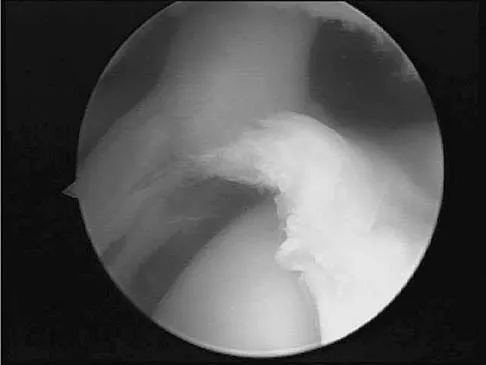

A baseball pitcher has intractable posterior and superior shoulder pain. The arthroscopic view seen in Figure 25 shows no Bankart or Hill-Sachs lesion and a negative drive-through sign. There are no signs of ligamentous laxity, but active compression and anterior slide tests are positive. Treatment should consist of